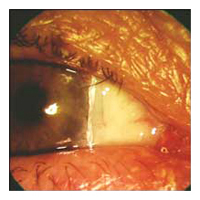

Before Pterygium Removal  After

Pterygium Removal

No-stitch Pterygium Surgery*

No-stitch pterygium surgery allows most patients to return to work

within one or two days of surgery. Research studies have shown that

patients undergoing no-stitch surgery had significantly less pain and

discomfort after surgery than those having traditional surgery. The

no-stitch technique also reduced surgery time by 20-30%.

Technique for No-stitch Pterygium Surgery

In no-stitch surgery, the patient is lightly sedated to ensure

comfort, and the eye is completely numbed, so there is no way to see

the surgery occurring and no sensation of discomfort. The abnormal

tissue is removed and replaced with a thin autograft or amniotic

membrane. Over the next 2-4 weeks, the eye gradually returns to a

normal appearance.